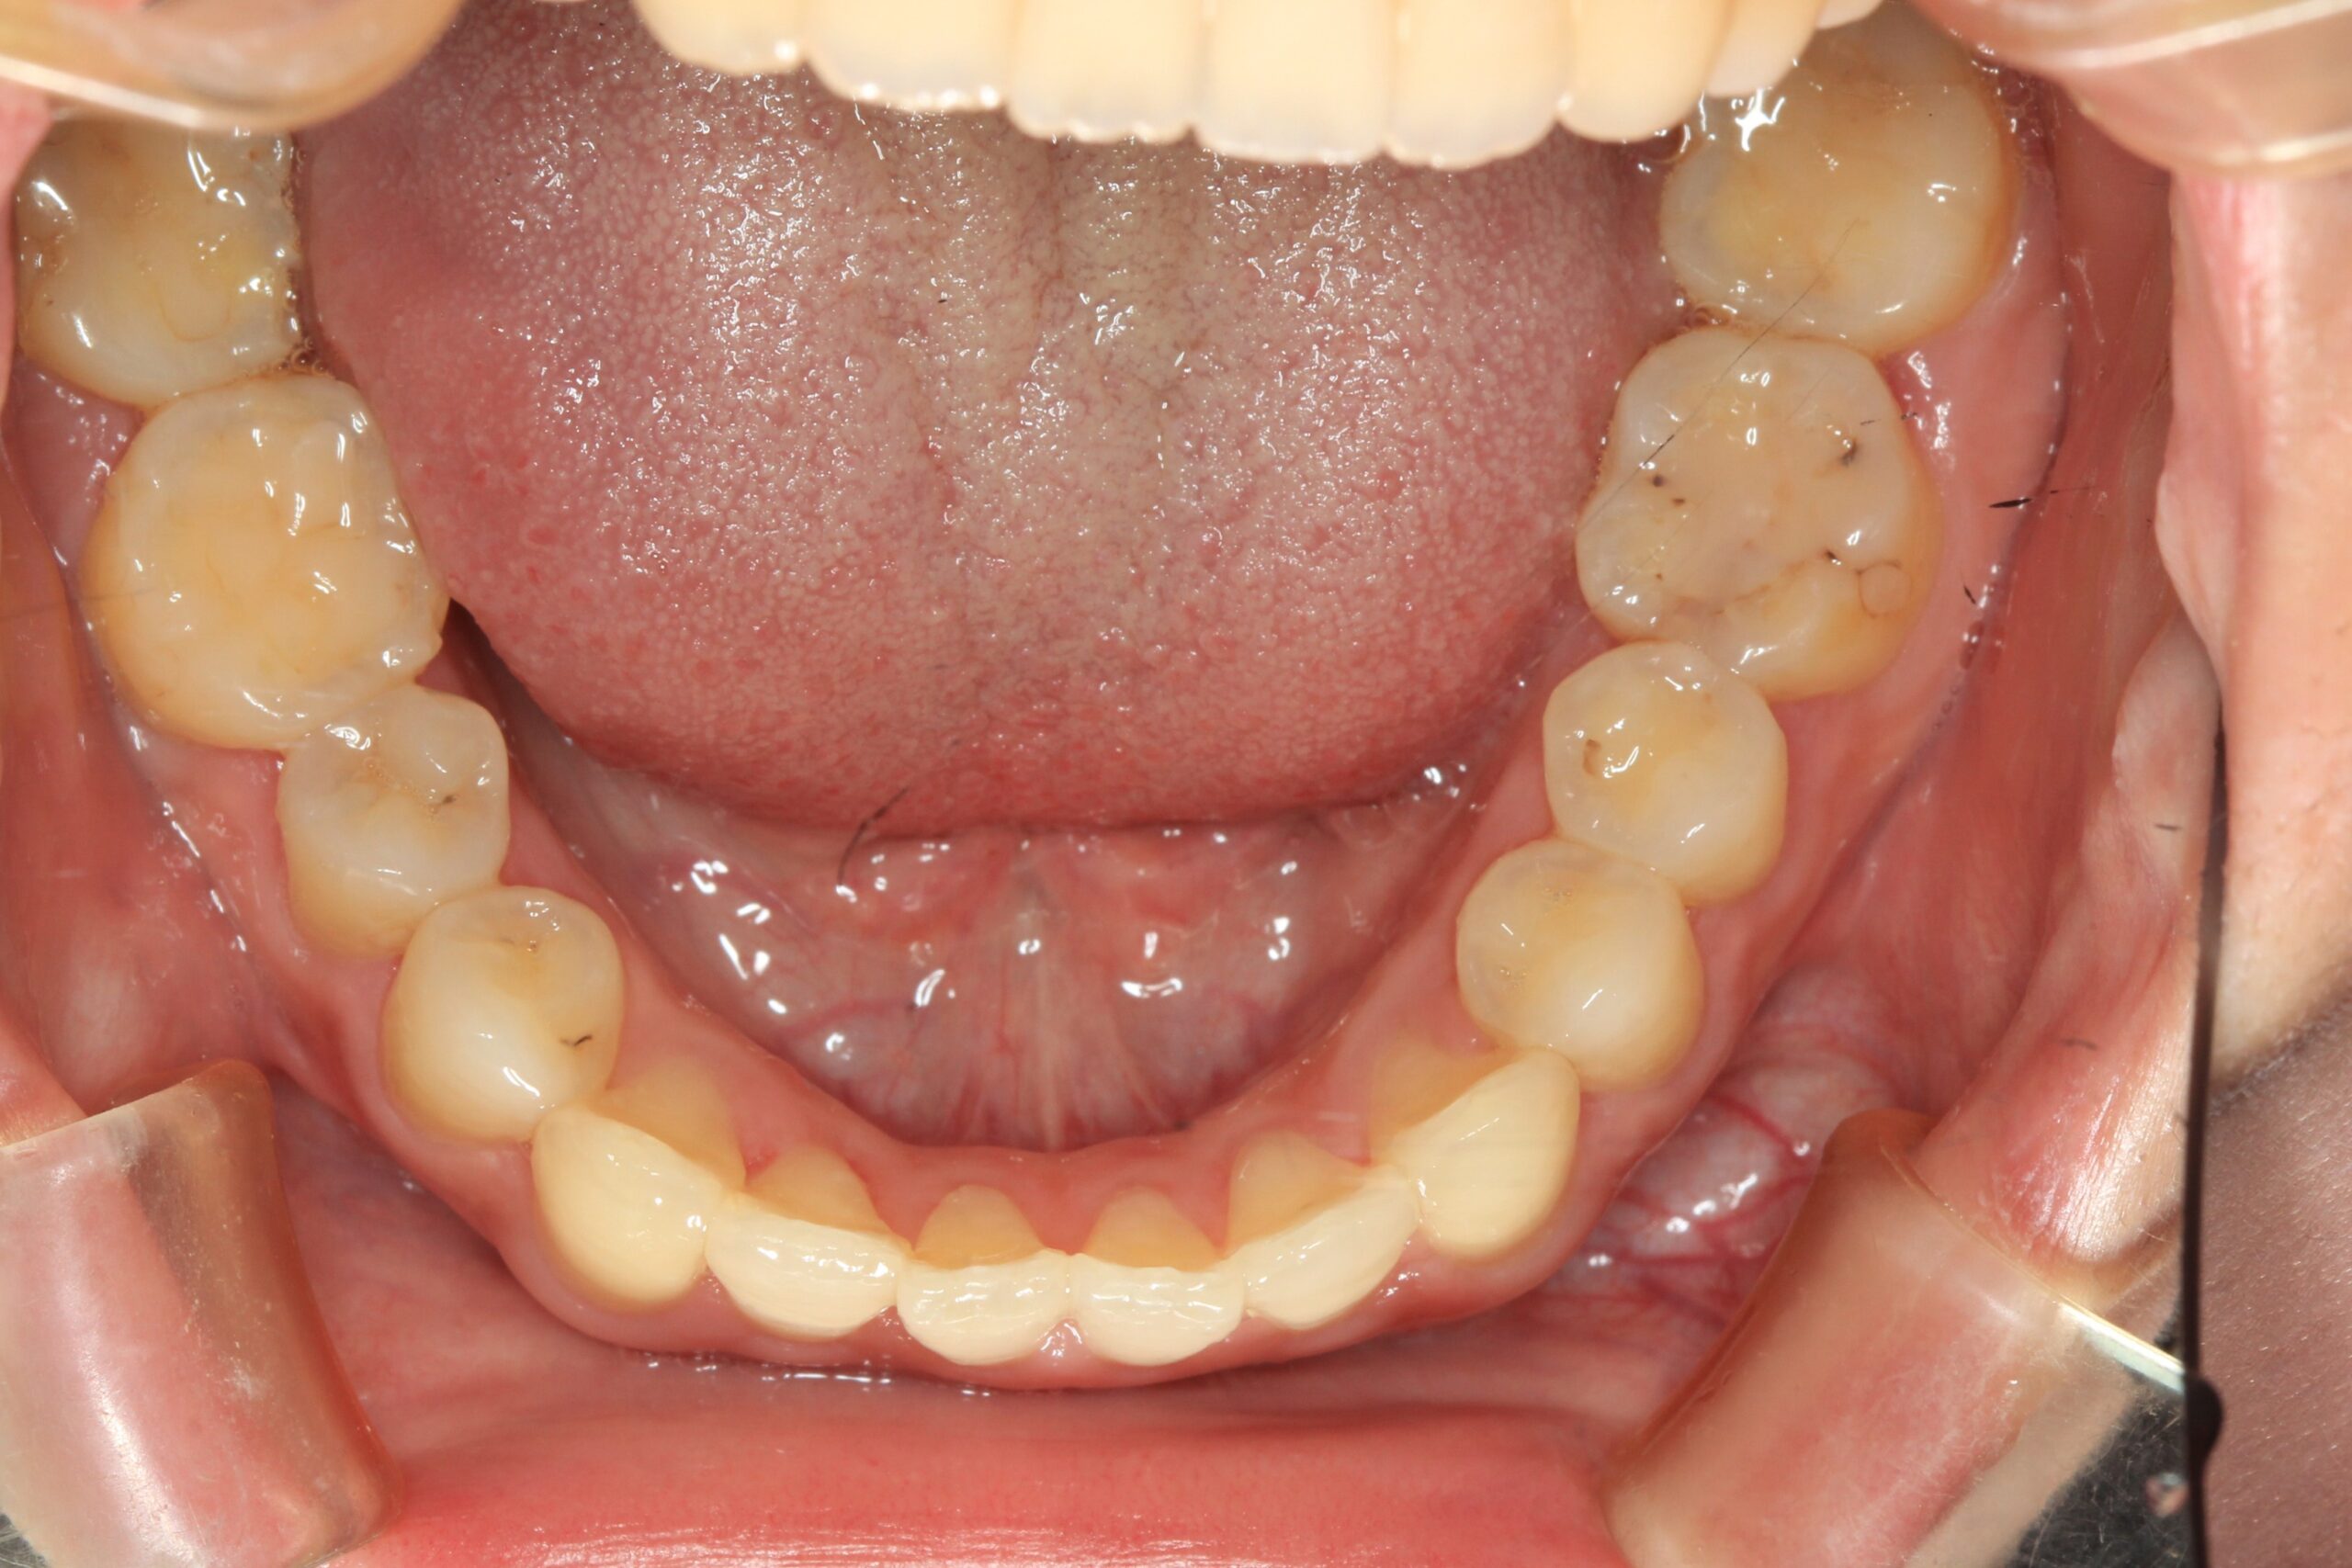

下顎もアーチを広げ綺麗に並びました。

出っ歯も綺麗に引っ込み、開咬も綺麗に改善しました。